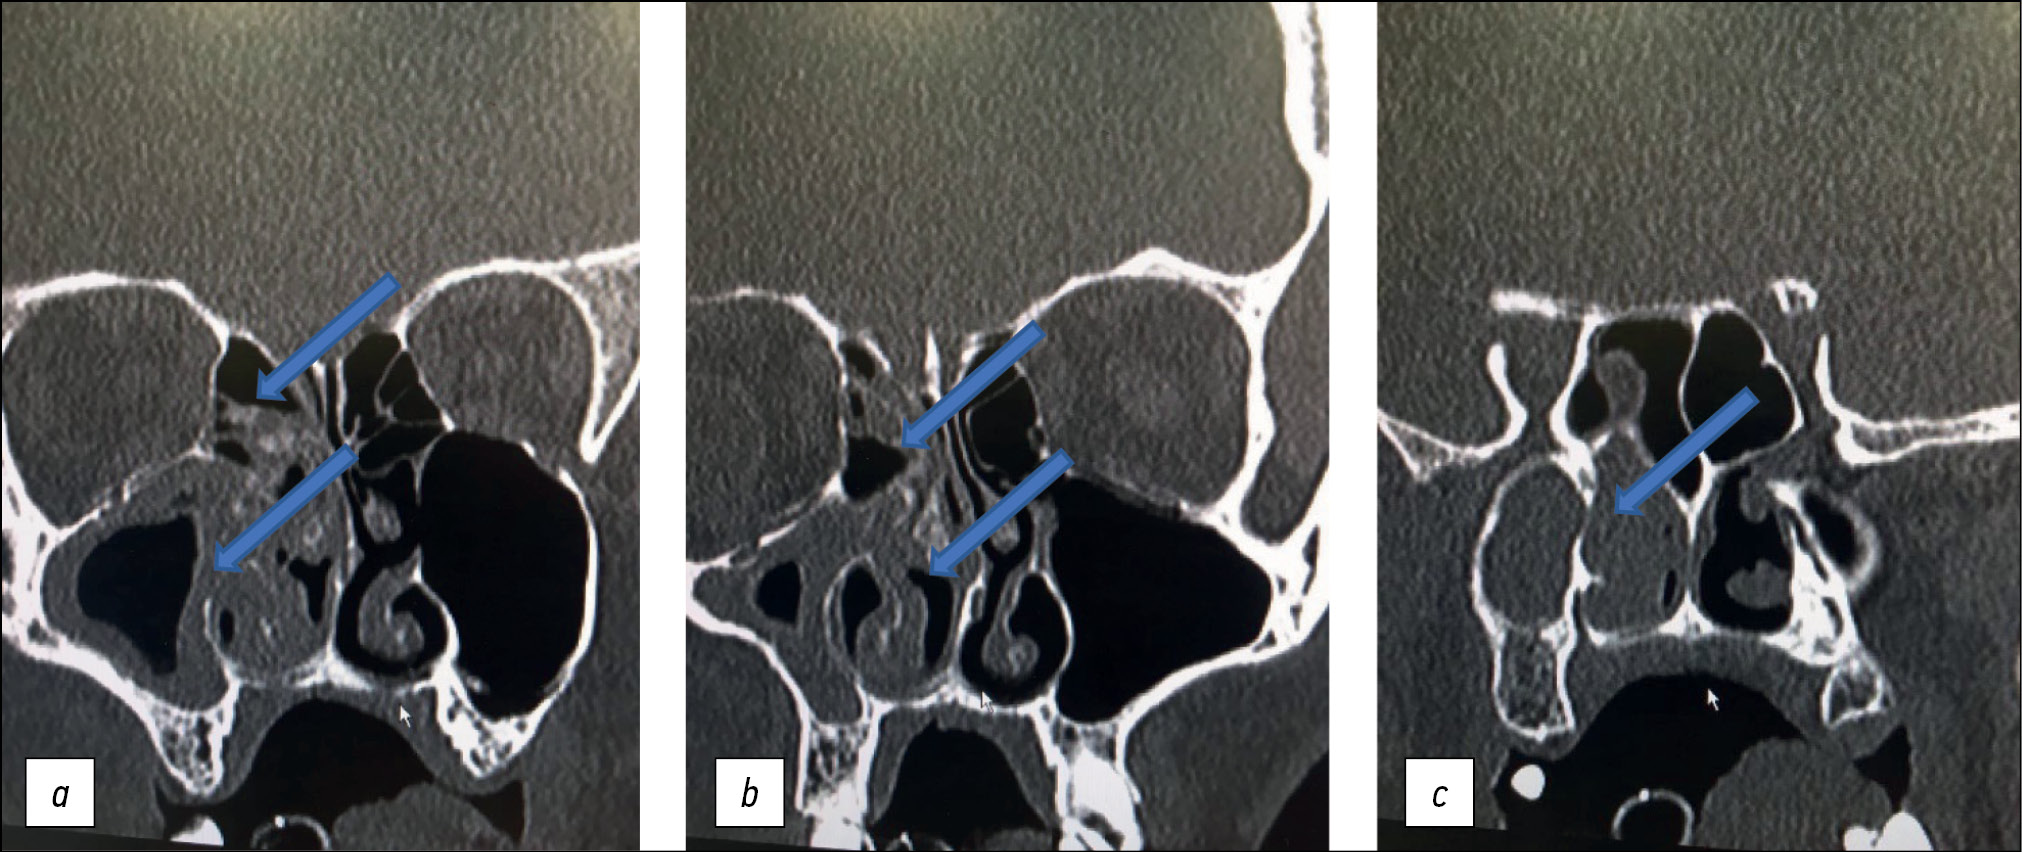

В связи с прогрессивно нарастающими проявлениями полиорганной дисфункции, угнетением сознания больной выполнена интубация трахеи, начата респираторная поддержка в режиме вспомогательной вентиляции лёгких. Повторно выполнена КТ головного мозга: органических изменений в веществе головного мозга, костно-травматических повреждений не выявлено. Клетки решётчатого лабиринта справа (рис. 2, a, b), правая верхнечелюстная пазуха субтотально заполнены патологическим содержимым (см. рис. 2).

Рис. 2. Тот же пациент. Срезы компьютерной томограммы: утолщение слизистой оболочки верхнечелюстной пазухи с блоком остеомеатального комплекса, утолщение слизистой оболочки клеток решётчатого лабиринта, слизистой оболочки полости носа в переднем (а), среднем (b) и заднем отделе (с) верхнечелюстной пазухи (стрелки).